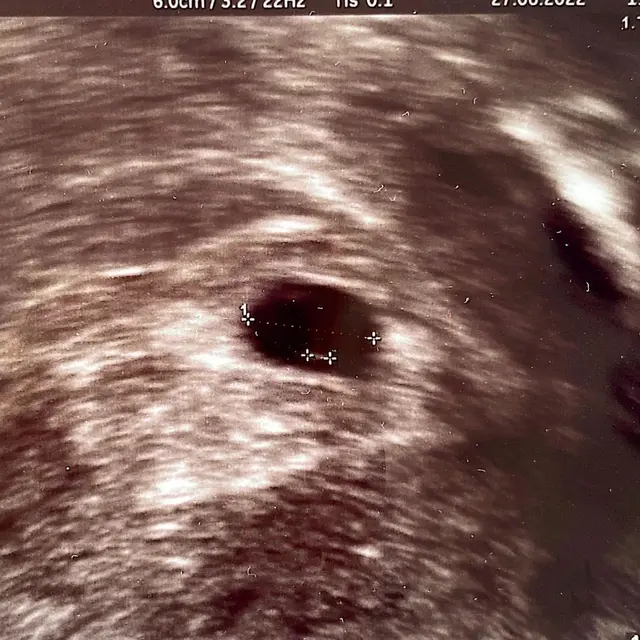

Melaui beberapa potret, Annisa bersama AHY dan putrinya. Perempuan kelahiran Bostom 40 tahun silam itu duduk di kursi roda. Sedangkan di belakangnya ada putri tunggalnya dan sang suami. Sedangkan foto lain, ada juga hasil USG perutnya.

Annisa Pohan hamil anak kedua, namun sayang pada saat usia kehamilannya tujuh minggu, janin tidak berkembang dan terpaksa harus dibersihkan.

Selain janin yang tidak berkembang, janin dalam perutnya juga tidak ada detak jantungnya.